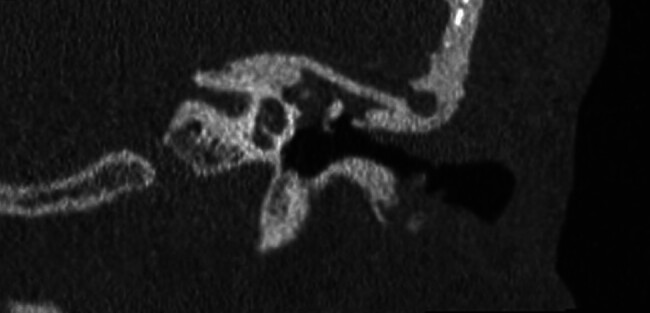

Objective: Occasionally, repair of tegmen defects can be complicated by the ossicular chain protruding above the floor of the middle fossa, which traditionally requires disarticulation and reconstruction of the ossicles to manage. This manuscript describes modifications of previously described techniques to address this surgical problem.

Participants: In this case series we present three patients with tegmen defect and encephalocele where the ossicles protruded over the floor of the middle fossa. In one instance, a "manhole cover" was created by concentrically layering hydroxyapatite cement around the tegmen defect and placing a piece of calvarium harvested from the bone flap over the defect. In another case, a "bony igloo" was drilled into harvested bone flap and placed over the defect, effectively creating a neo-epitympanum.

Results: No patients had recurrence of their encephalocele and/or CSF leak. No patients required manipulation of the ossicular chain intraoperatively. Hearing returned to normal in one case. Hearing worsened in one case, thought to be related to injury to the inner hair cells of the cochlear or cochlear nerve. Hearing did worsen in another case, thought to be related to pneumolabyrinth.

Conclusions: The "manhole cover" and "bony igloo" techniques are pragmatic solutions to this rare but complex surgical problem.